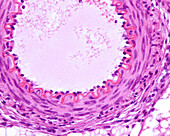

13742425 - Elastic arteries, light micrograph